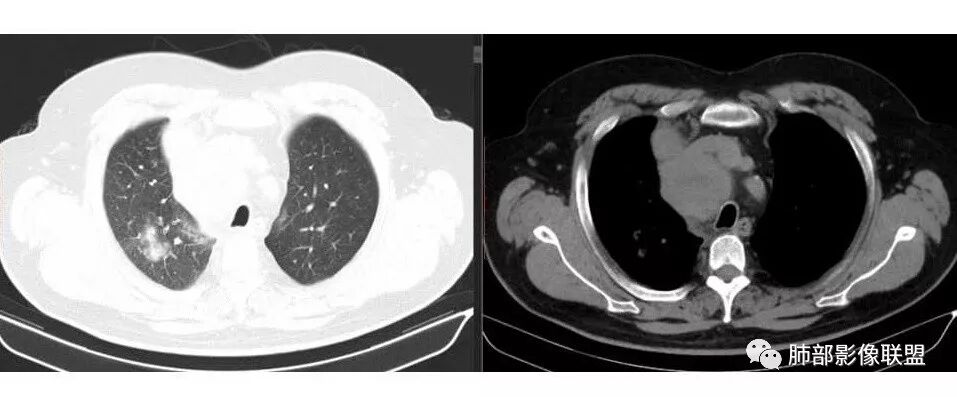

水晶石头: 患者中老年男性,以四肢乏力为症状表现,有吸烟史。胸部CT:右肺上叶不规则结节,周围见磨玻璃影,小叶间隔增厚。同侧纵膈明显淋巴结肿大。综合考虑恶性。存在小病灶大转移,冰冻纵隔,且有内分泌症状,首先小细胞癌可能大。监测排外淋巴瘤。

局限性中央间质增厚,考虑癌性淋巴管炎

部分区域有结节感

1.右肺上叶不规则结节影,右肺门及纵隔多结节并形成巨大块影,密度均匀,沿途支气管明显狭窄。

原发灶小或隐匿,肺门纵隔淋巴结异常增大,所谓“娘小崽大”常见于肺小细胞癌!

2.右肺小叶间隔增厚伴微小结节,提示癌性淋巴管炎。